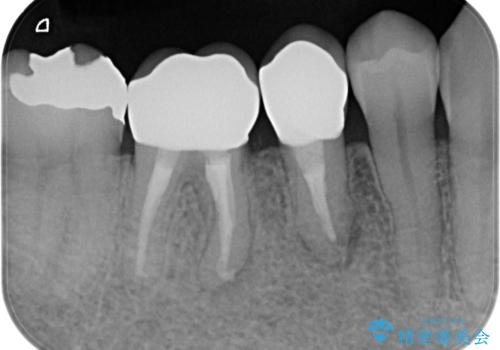

治療後、食べ物の挟まりは劇的に改善され、機能性に満足していただけると同時に見た目の審美性にも喜んでいただくことができました。